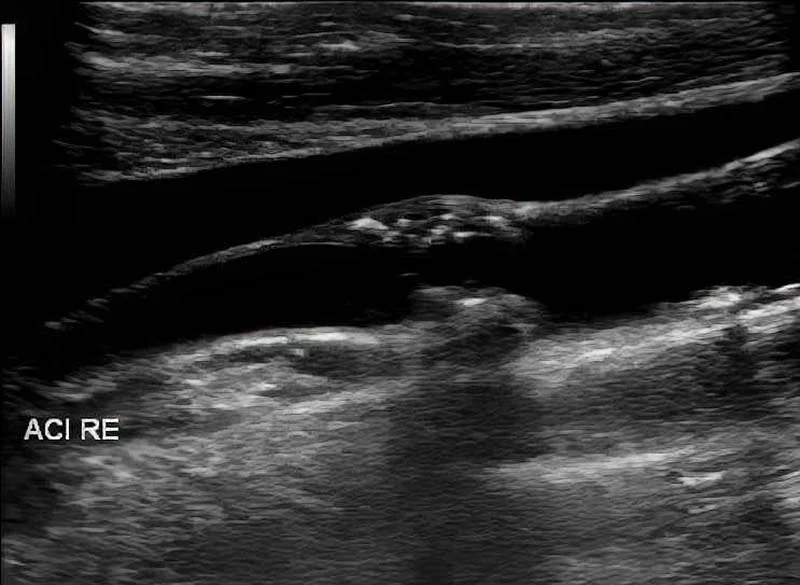

• Ultraschalluntersuchung der hirnzuführenden Gefäße

Ultraschallaufnahme eines hirnzuführenden Gefäßes mit arteriosklerotischem Plaque.